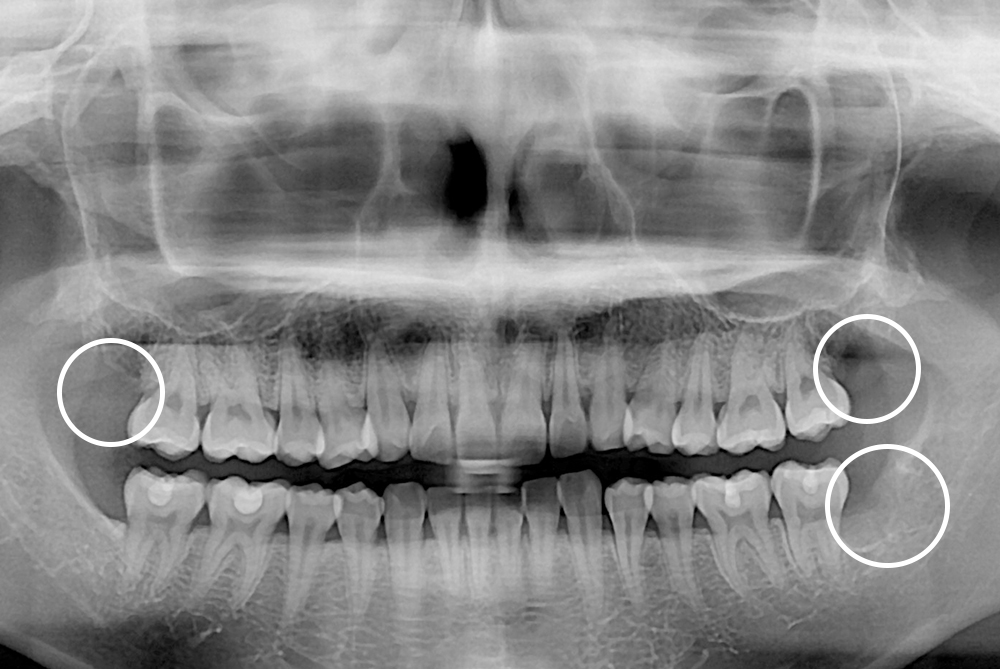

치료후 : 2022-03-18

세종치과는 구강악안면외과학 박사이신 원장님이 발치하는 치과입니다.